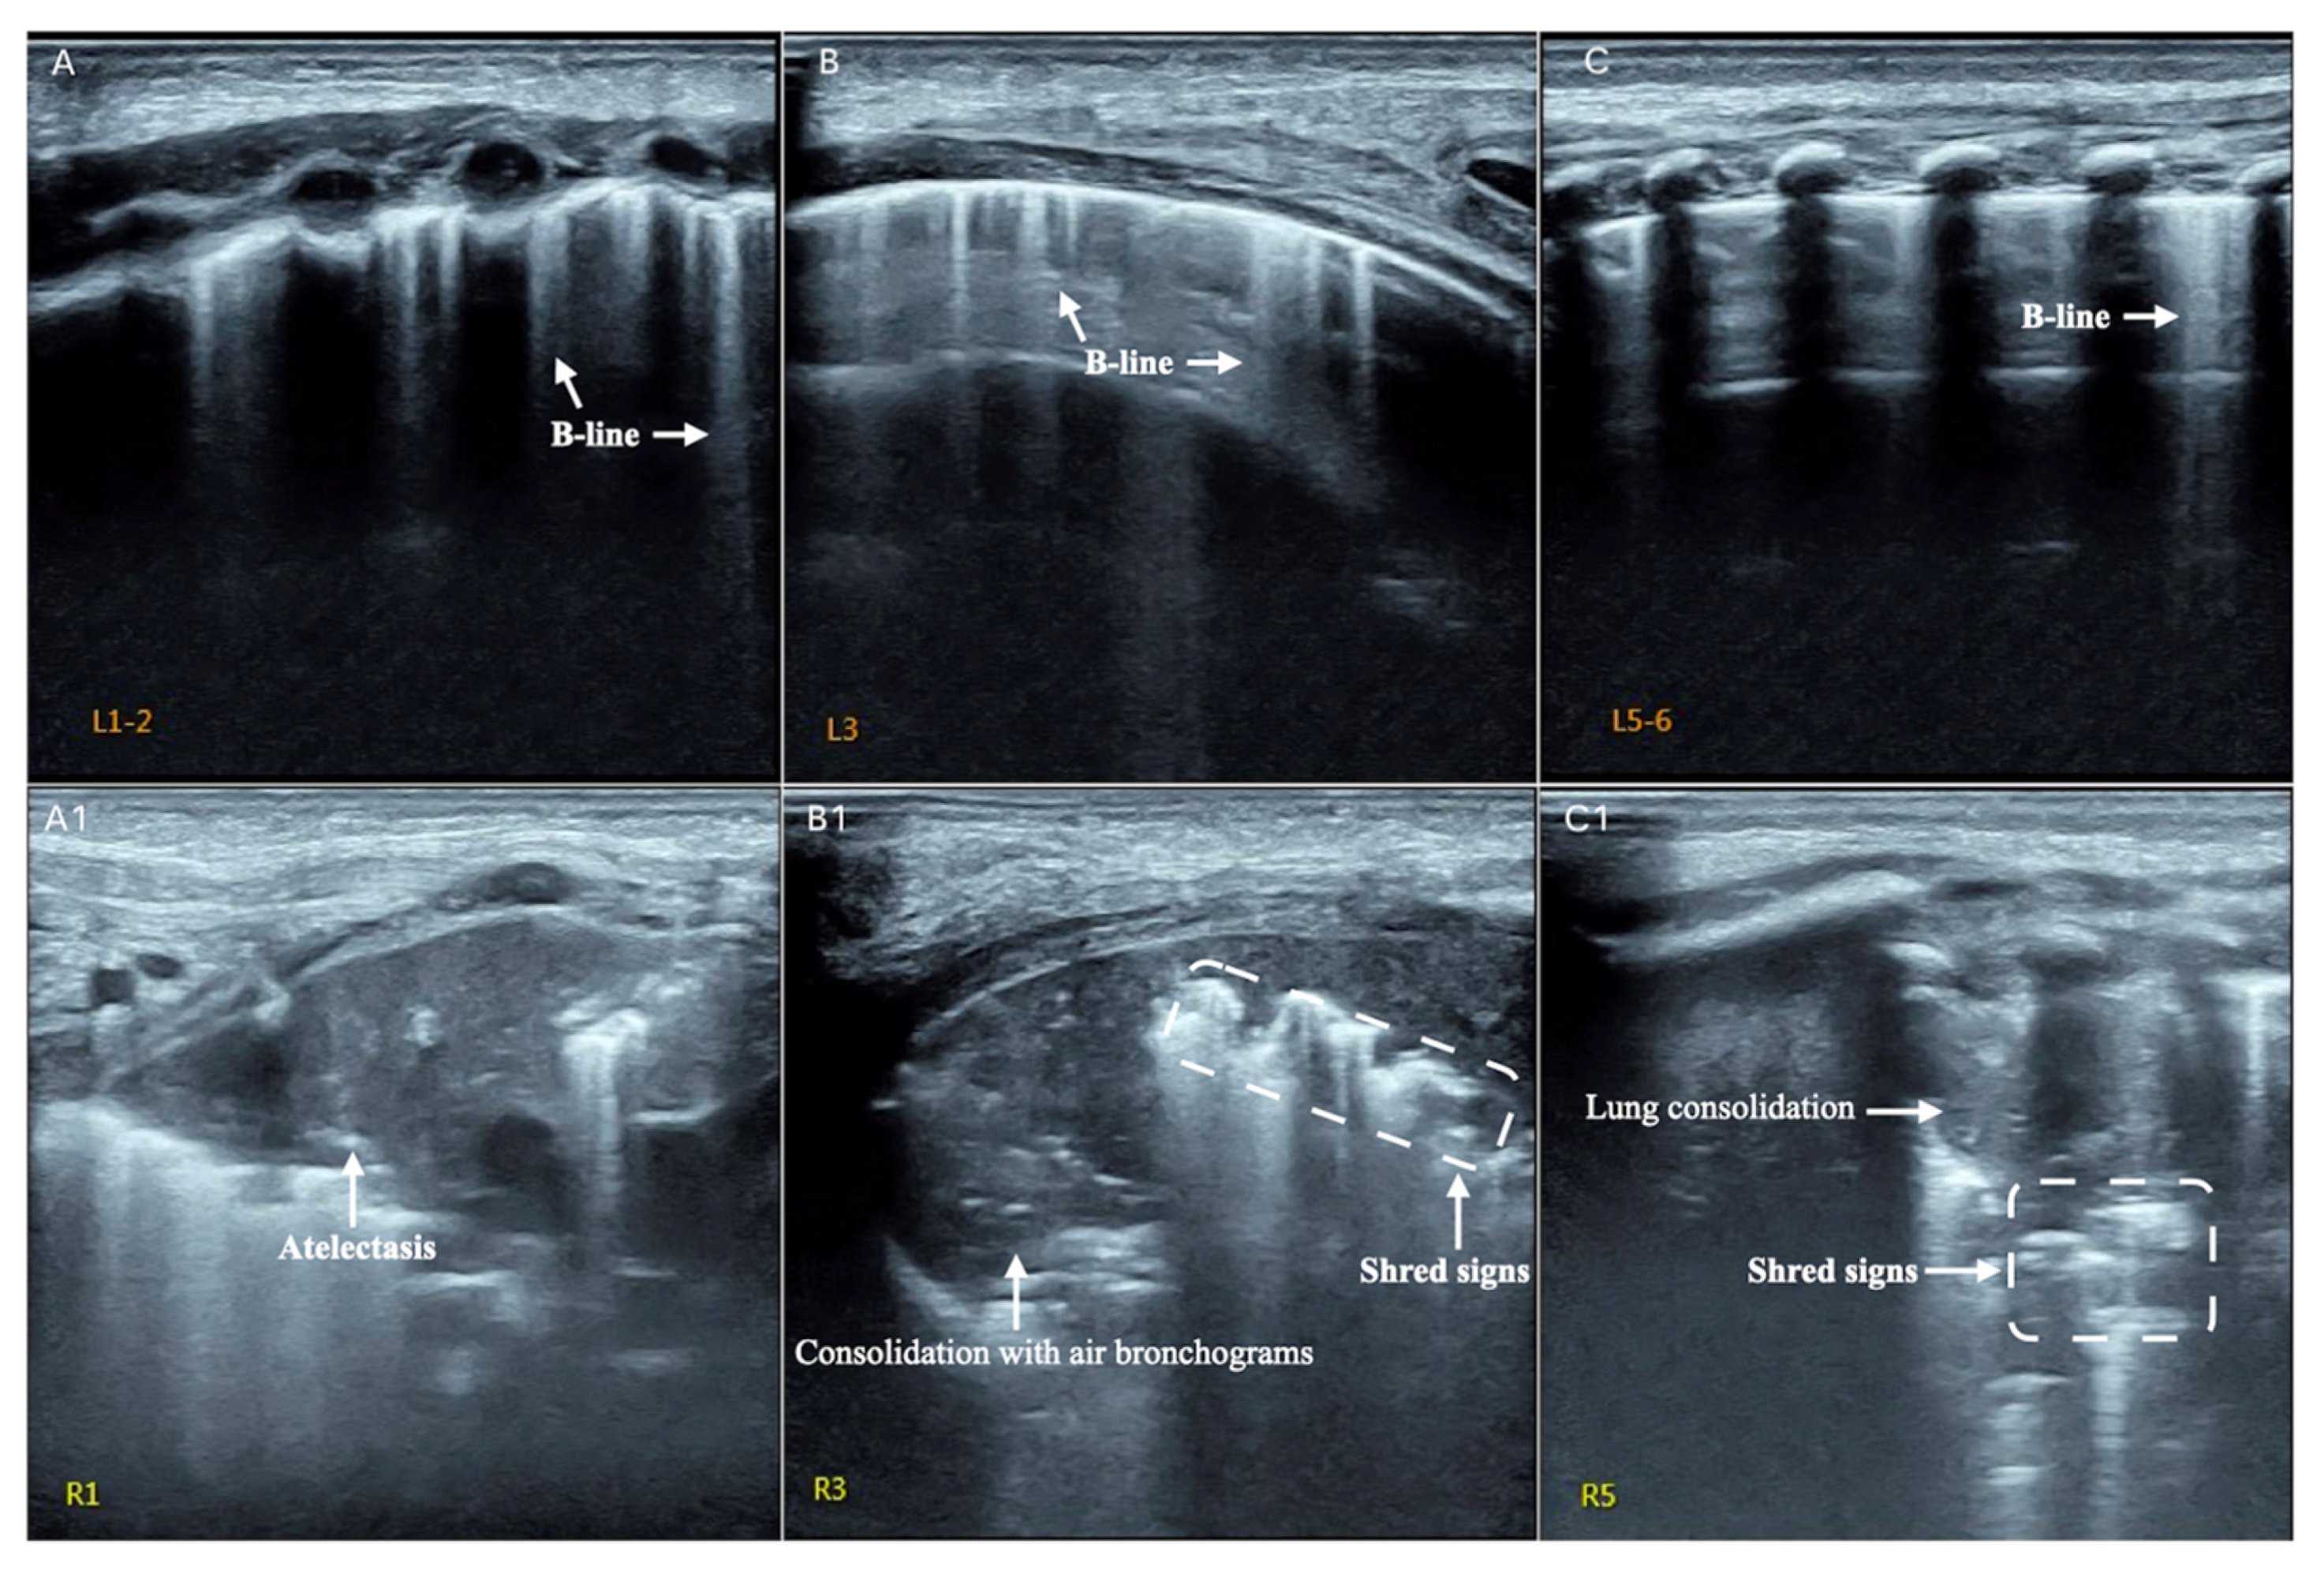

| B-lines | Vertical reverberation artefacts from the pleural line to the edge of the scree; laserlike, vertical hyperechogenic artefacts synchronized with pleural line [11,23,27] |

| Consolidation | Area in which lung tissue is de-aerated with density similar to parenchymal tissues [23] |

| Atelectasis | Type of consolidation shown as hyperechogenic tissue structure visualized as solid parenchyma with static air bronchogram [11,24] |